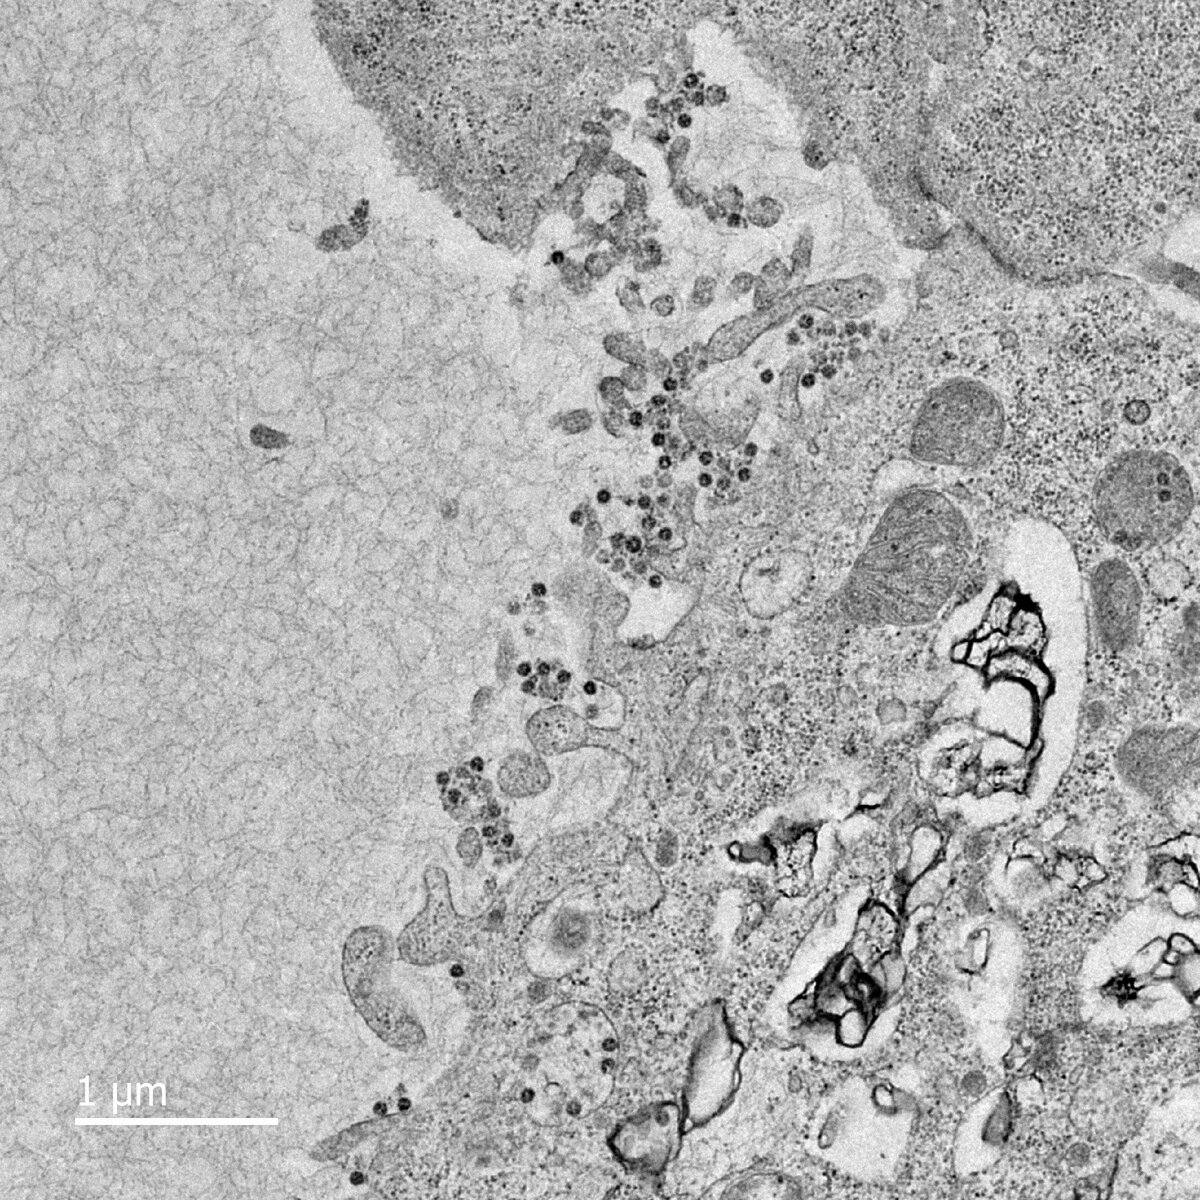

Что вы должны знать о вирусе Клетки, зараженные коронавирусом, взяты из образца пациента и выращены учеными в Гонконге. Клетки, зараженные коронавирусом, взяты из образца пациента и выращены учеными в Гонконге. Медицинский факультет Гонконгского университета Мы еще многое не знаем о коронавирусе, и ученые всего мира стремятся собрать данные и разработать лечение. Вот что мы можем вам сказать: Есть ли лекарство? Не в данный момент. Исследователи успешно выращивают вирус в лаборатории, что является важным шагом на пути к разработке вакцины, но может пройти год или больше, пока она не станет доступной. Каковы симптомы? Симптомы коронавируса могут выглядеть как грипп, лихорадка, проблемы с дыханием. Если вы показываете эти симптомы и недавно уехали в Китай, или были в контакте с кем-то, кто посещал, специалисты советуют сходить к врачу. Как распространяется вирус? Считается, что вирус распространяется от человека к человеку через дыхательные капельки, выделяющиеся при кашле или чихании, но неясно, когда именно человек становится заразным. В настоящее время нет никаких доказательств того, что вирус находится в воздухе, то есть, например, он не распространяется через большую комнату. Кто подвержен риску заражения? Люди всех возрастов могут быть заражены этим вирусом, но пожилые люди и люди с уже существующими заболеваниями особенно уязвимы для серьезных осложнений. Как я могу защитить себя? Примите те же меры предосторожности, что и во время сезона гриппа. Часто мойте руки с мылом и водой, прикрывайте нос и рот, когда вы чихаете или кашляете, избегайте тесного контакта с людьми или большими скоплениями людей и носите маску для лица. Безопасно ли путешествовать? Авиакомпании приостановили полеты, и тысячи иностранных граждан в китайском городе Ухань были эвакуированы обратно в свои страны. Многие страны, в том числе США, рекомендовали не ездить в Китай.